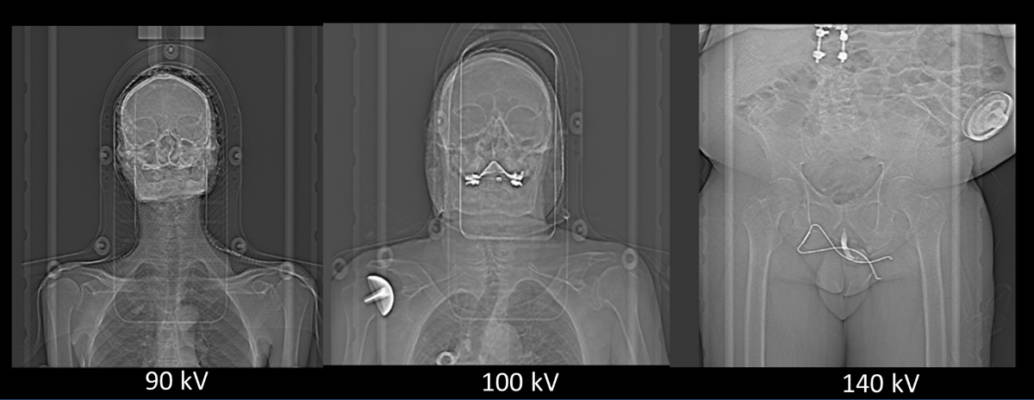

Mean kV selected for diÂerent thicknesses of breast using AUTOKV mode ...

CT Dose Reduction Strategies Experience with Care (Auto) kV

Clinical application of 100 kVp acquisition with an iterative ...